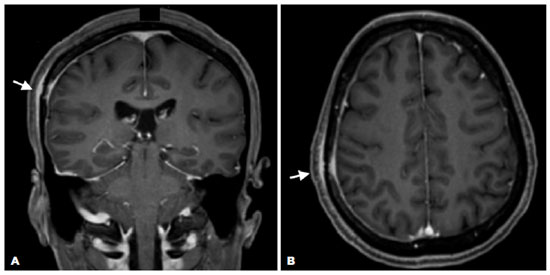

MRI revealed a lesion with impregnation by contrast in the right frontoparietal skullcap and a smooth dural enhancement along the right convexity, suggestive of an inflammatory-infectious process (Figure 2). The cerebral parenchyma and optic nerve-sheath complexes demonstrated no changes. The CSF analysis revealed negative VDRL and FTA-ABS test results, no pleocytosis (5 leukocytes/mm3), and protein levels within the reference values (36,00 mg/dL). The opening pressure was 17 cm H2O.

Admission for intravenous administration of aqueous crystalline penicillin G for 14 days followed, with gradual improvement of signs and symptoms throughout hospitalization (Figure 3A and B). Two months after the treatment, the patient’s VA was 20/20 in OU, resolution of the RPE nodularities was observed on OCT (Figure 3C and D), and complete resolution of the dural enhancement and skull lesion were visualized on MRI (Figure 4). Follow-up in the ophthalmology and infectology departments were maintained.

Bone involvement is common in syphilis owing to the high affinity of the T. pallidum to osseous structures. The skull and long extremity bones are the most commonly involved bones, with symptoms consisting of headache and local pain, respectively(8,9). Osseous involvement can be detected by imaging examination, and enhancement of the adjacent periosteum and dura-mater can be observed on MRI(8).

In face of optic disc edema and dural enhancement on MRI, one could have raised the hypothesis of pachymeningitis as a differential diagnosis in the reported case. However, a normal opening pressure, negative FTA-ABS test result, negative VDRL, absence of pleocytosis, and normal protein levels in the CSF made the diagnosis of pachymeningitis unlikely.